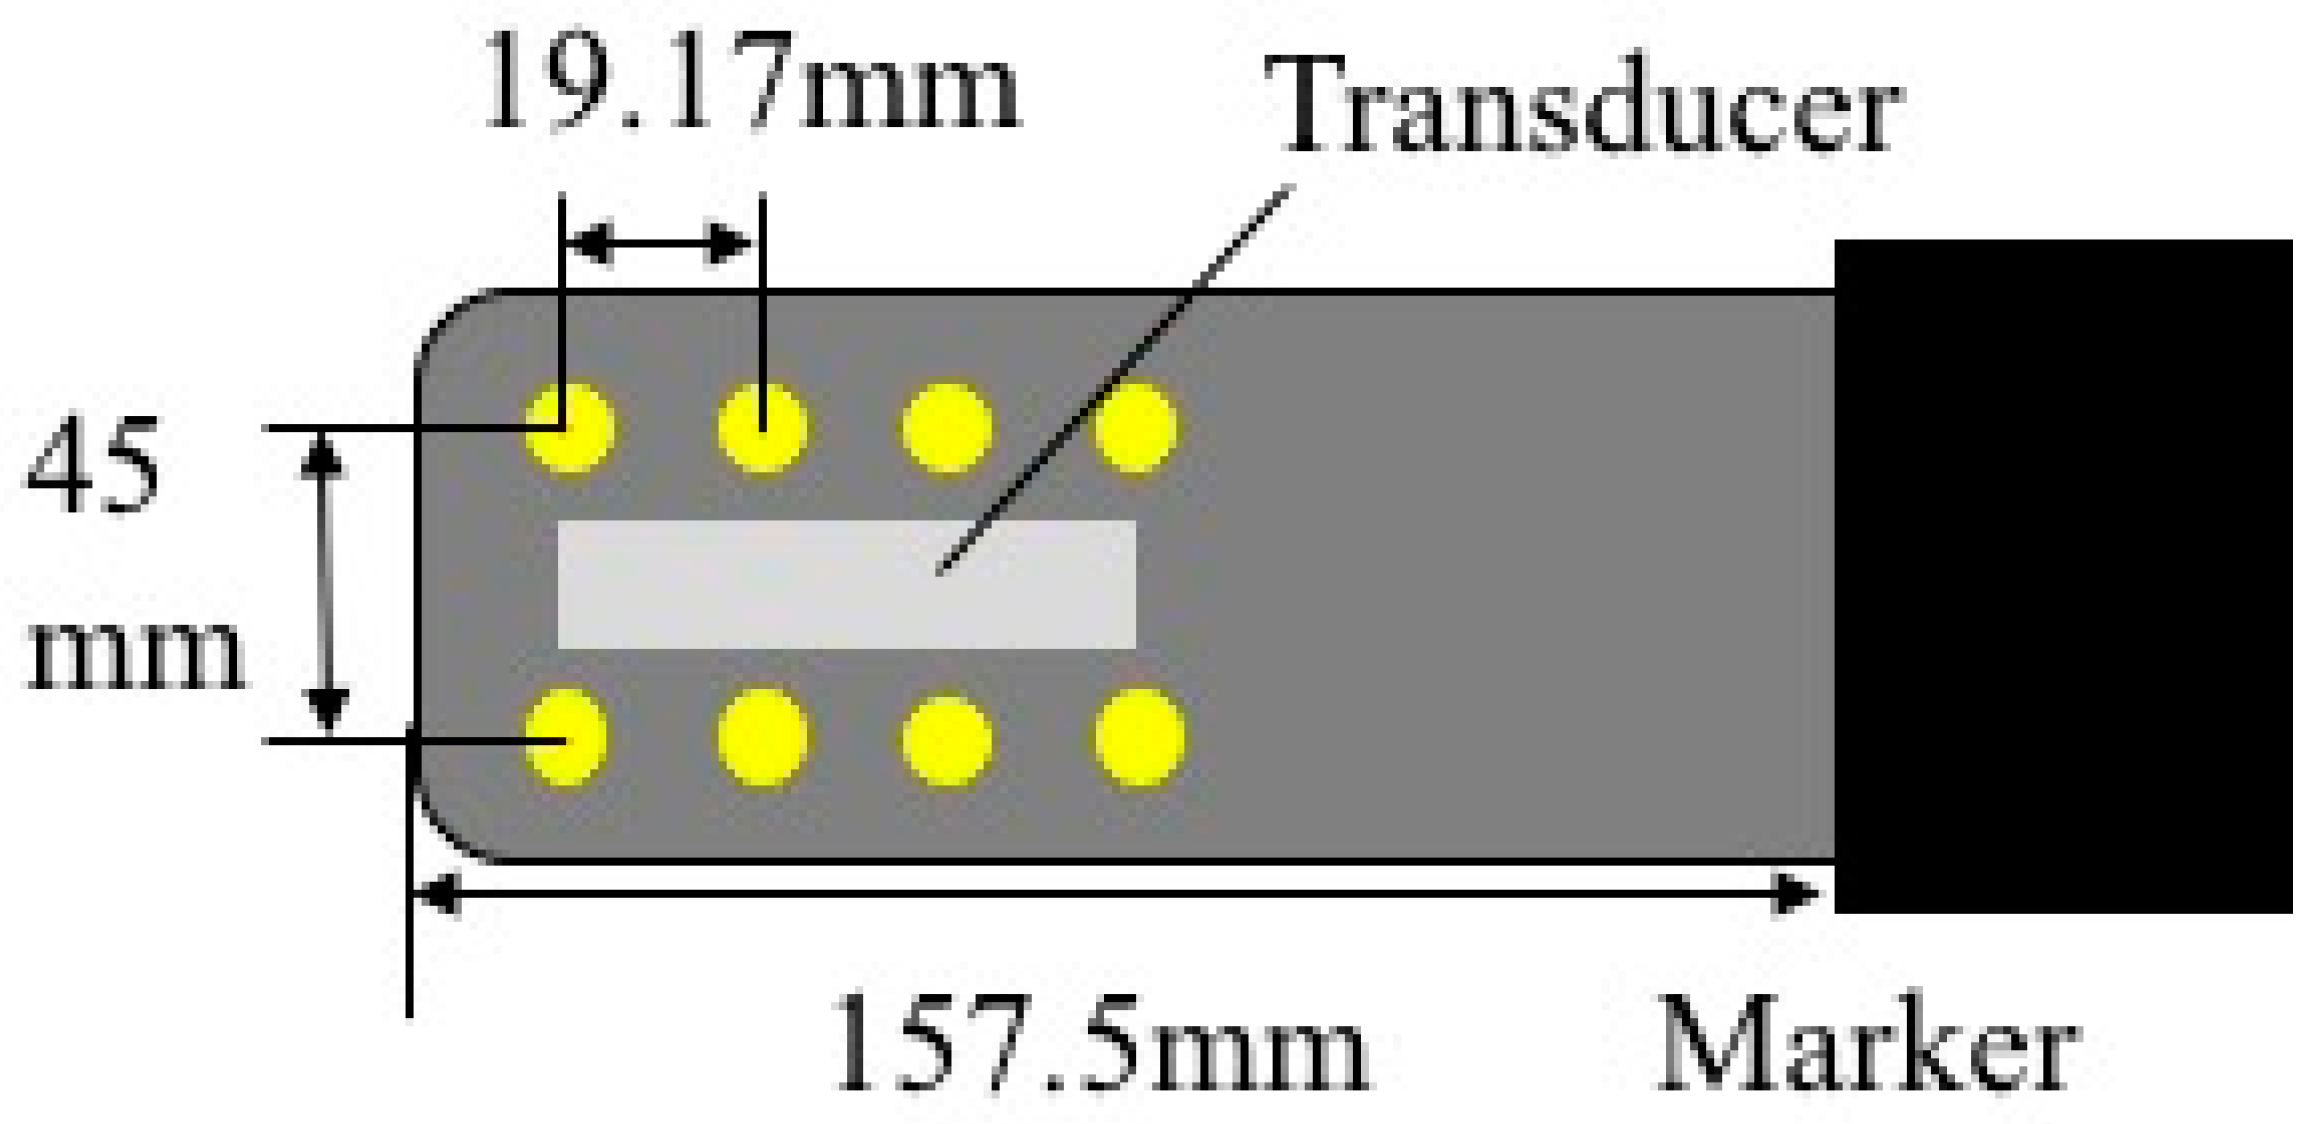

2.1. Ultrasound Probe for Use in MRI